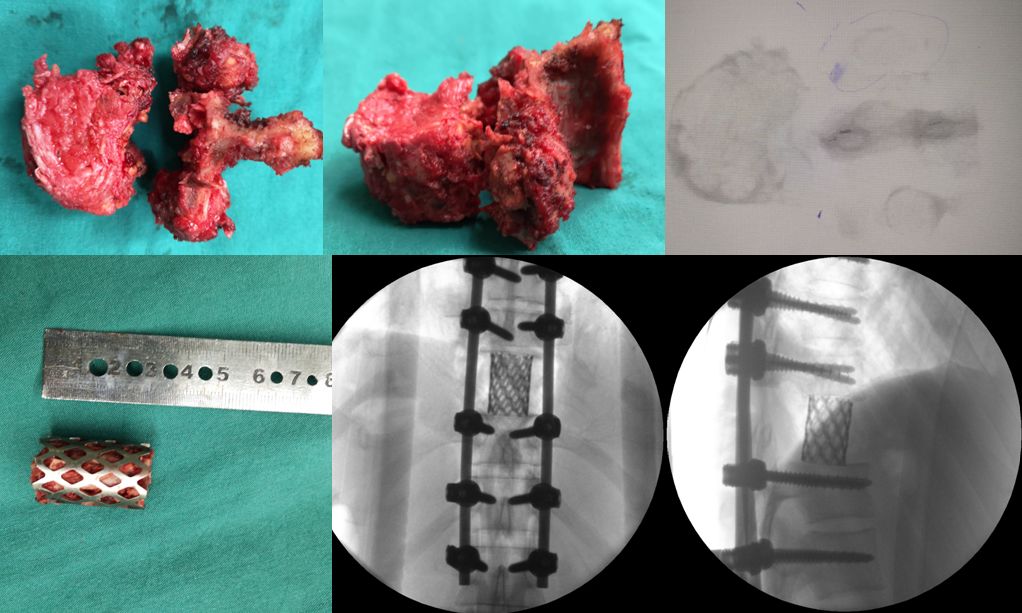

由于肿瘤周围紧挨着神经、脊髓和血管,手术既要保持肿瘤组织的完全切除,又不能牺牲重要结构,因此每一步都需要小心翼翼,张顺聪教授和丁金勇教授紧密合作,不敢有一丝懈怠,将肿瘤椎体一点一点的分离而不损伤周边正常组织。手术整整进行了9小时10分钟,在张顺聪教授和丁金勇教授专业细致的操作下,患者最终有惊无险的完成整个手术,肿瘤椎体被完美的切除,术后疗效满意。

脊柱肿瘤被完美切除,内植物位置满意